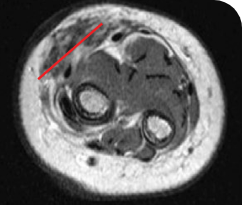

Reduction in tumor burden1

MRIa imagery of the brain. Red line indicates the maximum dimension.1

aMRI, magnetic resonance imaging.

PATIENT CASE:

- 5-month-old with IFSa

- Confirmed PRa after 4 cycles of VITRAKVI® (larotrectinib)

- Referred for definitive limb-sparing surgery after 6 cycles

of VITRAKVI; achieved pCRa,b

Response to VITRAKVI1

- Patient achieved a confirmed partial response after 4 cycles of VITRAKVI with a 45% reduction in tumor burden